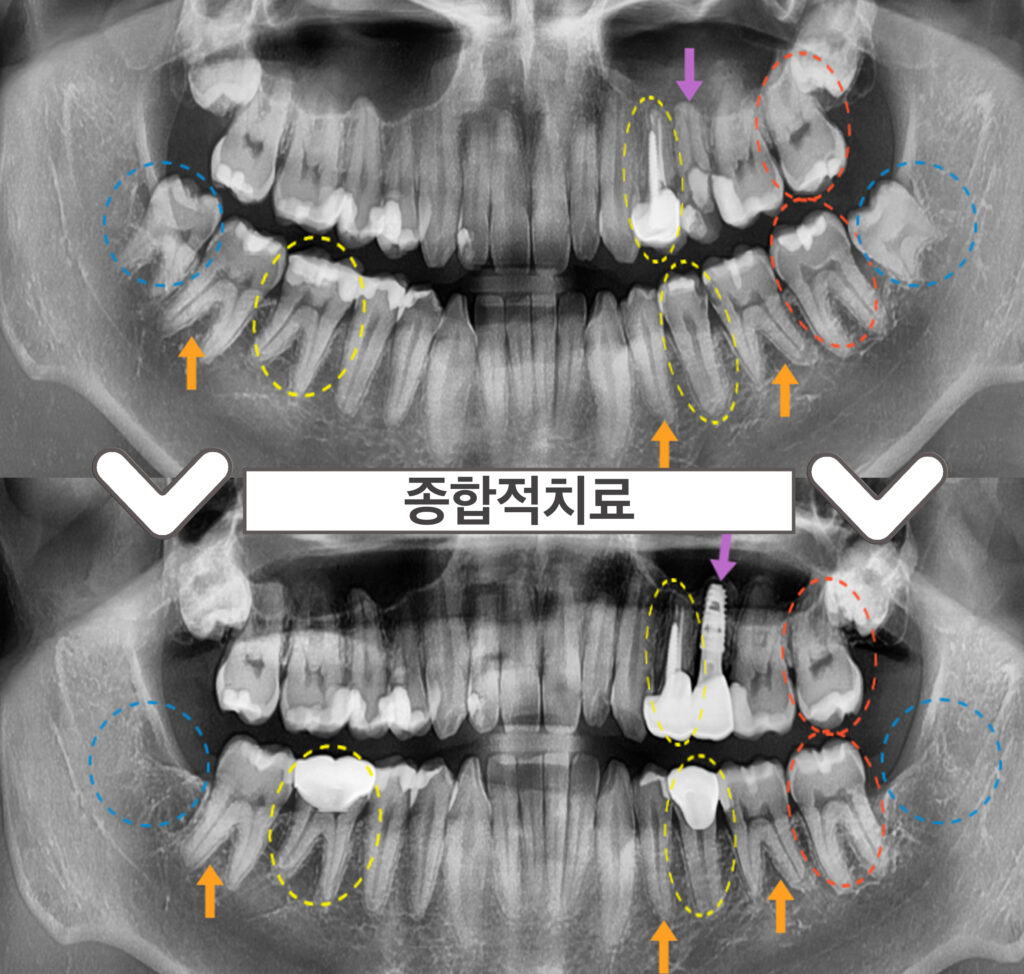

오늘 소개해드릴 분은 30대 남성분으로,

왼쪽 위아래 어금니와

오른쪽 아래 어금니가

아파서 치료를 원하시며

아래 사랑니도 빼고 싶다며

본.원을 찾아주셨는데요.

구강 내 상황을 체크해 보니

치아와 치아 사이에

충치가 있는 부위를

다수 관찰 할 수 있었으며,

기존 크라운 보철물과

아말감 수복물 하방으로

2차 우식이 관찰되는 부위도

확인할 수 있었습니다.

오른쪽 위 치아를 제외하고는

다수의 치아의 치료가 필요하였답니다..!

✔ 왼쪽 위 두 번째 작은 어금니(#25) – 보라색 화살표

: 발치 후 즉시 임플란트

✔ 왼쪽 위 첫 번째 작은 어금니(#24),

왼쪽 아래 두 번째 작은 어금니(#35),

오른쪽 아래 첫 번째 큰 어금니(#46) – 노란색 동그라미

: 크라운 (필요시, 신경치료)

✔ 왼쪽 위아래 두 번째 큰 어금니(#27,37) – 빨간색 동그라미

: 기존 아말감 제거 후 인레이

✔ 왼쪽 아래 첫 번째 작은 어금니(#34), 큰 어금니(#36),

오른쪽 아래 두 번째 큰 어금니(#47)- 주황색 화살표

: 충치 제거 후 인레이

✔ 왼쪽, 오른쪽 아래 사랑니 (#38,48) – 파란색 동그라미

:발치

✅ 전 > 후 ✅

(2023.02.03 ㅡ> 2023.08.26)